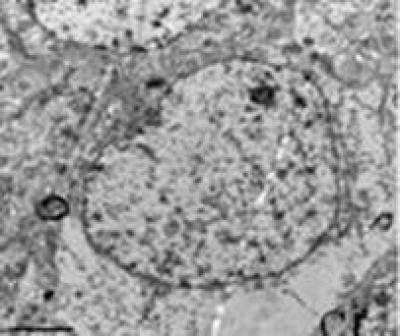

After administration of dl-3n-butylphthalide, cortical neurons in rats with diffuse brain injury have a clear nucleolus, smooth karyotheca, better con-tinuity, regular mitochondria shape, mostly tightly and regularly arranged complete cristae, and less shedding matrix granules.

(Photo Credit: Neural Regeneration Research)